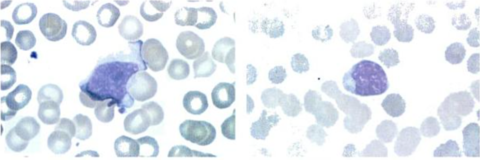

Tanto los linfocitos T, como B pierden su morfología al ser altamente activos, llamándoles linfocitos "atípicos" o células de Downey. Estos por su forma llegan a confundirse con monocitos, la diferencia está en la mayor condensación de los cromosomas de los linfocitos (Rodak, 2004). Los linfocitos T al estar activos son difíciles de diferenciar, pues tienen a perder y volver a adquirir los receptores, con dos objetivos: 1. ser más específicos y 2. proliferarse cuando no posean los receptores en sus membranas (Rodak, 2004).